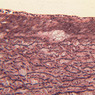

Veins are generally divided into small, medium, and large categories, though this division is not as readily based upon structural differences as among arteries. Examine a section of medium-sized vein (B-83, spermatic cord [2.5x, 10x, 20x-labeled, 40x] [10x, 20x, 40x] [2.5x, 10x, 20x, 40x]). The tunica adventitia, composed mainly of collagenous fibers cut obliquely or transversely, may be the thickest of the three coats. A thin internal elastic membrane can be seen in places around the vessel, but it is much less prominent than the membrane of the companion artery. No external elastic membrane is distinguishable in the vein. Compare the features of artery and vein: thickness of wall, size of lumen, amount of musculature, etc. The vein has a relatively wide lumen and a thin wall because it carries large volumes of blood at low pressures.

Large veins have a very narrow tunica intima and only a few layers of muscle and fibers in the tunica media (A-28, H&E [2.5x, 10x-labeled, 20x, 40x], AF [2.5x, 10x, 20x, 40x]). Its chief coat, as in smaller veins, is the tunica adventitia, but in this case, the coat is composed mostly of longitudinal muscle fibers. Some other large veins, particularly those of the cranial cavity, lack muscle and thus differ from the venae cavae. The structure of veins generally and large veins in particular is more variable than arterial structure.